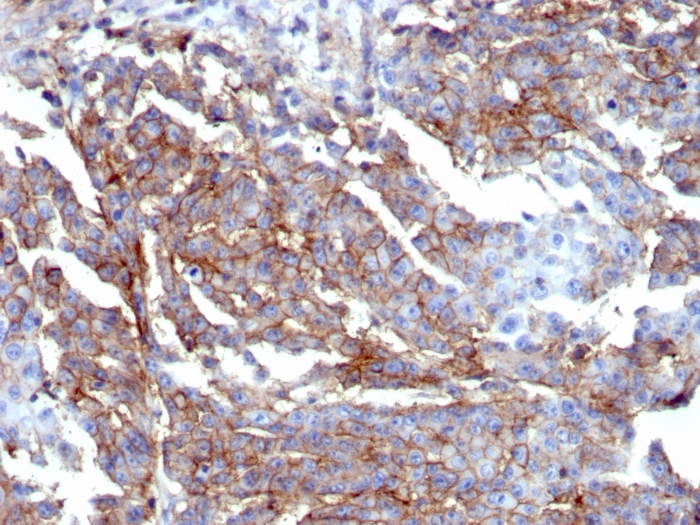

Formalin-fixed, paraffin-embedded human breast stained with CD44 Recombinant Rabbit Monoclonal Antibody (HCAM/6459R).